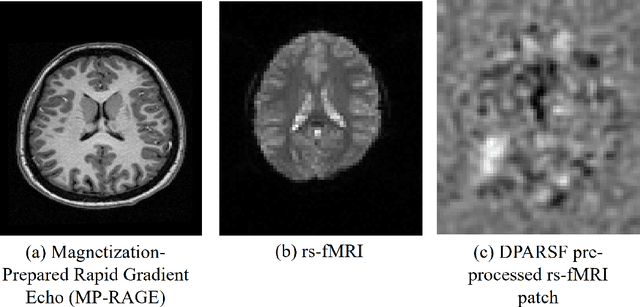

Abstract:Quantifying functional connectivity (FC), a vital metric for the diagnosis of various brain disorders, traditionally relies on the use of a pre-defined brain atlas. However, using such atlases can lead to issues regarding selection bias and lack of regard for specificity. Addressing this, we propose a novel transformer-based classification network (AFBR-KAN) with effective brain function representation to aid in diagnosing autism spectrum disorder (ASD). AFBR-KAN leverages Kolmogorov-Arnold Network (KAN) blocks replacing traditional multi-layer perceptron (MLP) components. Thorough experimentation reveals the effectiveness of AFBR-KAN in improving the diagnosis of ASD under various configurations of the model architecture. Our code is available at https://github.com/tbwa233/ABFR-KAN